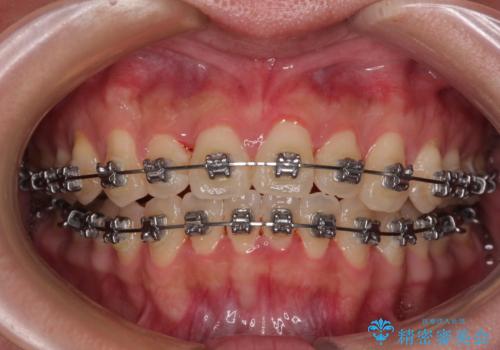

- メタルブラケット

- 1年4ヶ月

- 上下前歯のデコボコやクロスバイトを気にして来院された患者様です。

上顎歯列が下顎の歯列に対して狭小であり、一部下顎の奥歯が上顎よりも外側に位置している状態でした。

上顎の急速拡大装置を使用して上顎骨を側方に拡大することで上顎歯列を拡大し、下顎歯列も拡大できるようにすることで、歯列を整えることとしました。